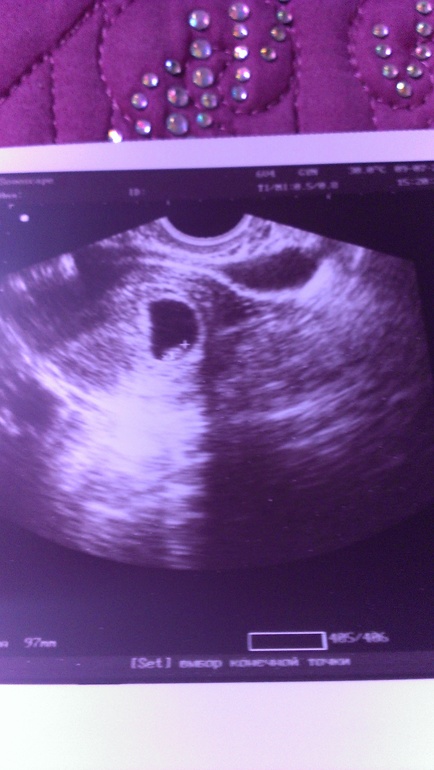

УЗИ 7 недель

Вопросы про УЗИ, обследования и анализы: что, где, как, когда?здравствуйте Узи ровно в 7 недель.. Может кто разбирается. Сказали, что все нормально. Но не пойму, почему на узи два пятна. Обратила внимание только дома. Что это может быть.Почему-то начала думать про гематому и т.п. :(

Уменьшенное фото.может это яйчник попал в кадр....обычно его тоже смотрят на наличие кисточек. ....

Фасолинка рядом с крестиком на снимке это и есть ваша ляля))) А вот что за второе темное пятно я, к сожалению, не в курсе.

Может двойня, а во втором ПЯ не видно эмбриона? Вообще, лучше еще раз с фоткой к врачу сходить...